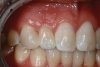

There are a number of requirements to achieve a successful bonded bridge. First, the edentulous site must be approximately the same width as the contralateral tooth. There also must be adequate soft tissue to provide esthetic emergence contours for the ovate pontic. Some clinicians may be concerned that the ovate pontic will not adequately maintain the soft tissue and, over time, the tissue will shrink away from the pontic. However, the soft tissue under an ovate pontic has been shown to be quite stable long-term.39 An example of this is shown in Figure 15.

Fig 15. Four-year postoperative photograph of zirconia bonded bridge replacing tooth No. 7.

Figure 15

Fig 16. Occlusal view of the zirconia bonded bridge in Fig 15 at 4-year postoperative showing one wing on the canine abutment and a small anti-rotation extension from the pontic onto the distolingual surface of tooth No. 8.

Figure 16